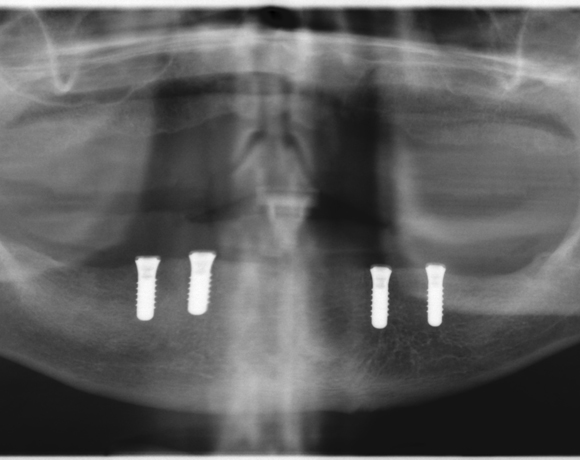

Fixierung einer Unterkiefervollprothese mit vier Implantaten

Mit Implantaten und dem Locatorsystem lassen sich Prothesen gut fixieren und geben einen guten Halt zum Essen und Sprechen

Ein Projekt aus dem Jahr 2014

61 jähriger Patient, im Ober- und Unterkiefer mit Vollprothesen versorgt. Der Patient litt darunter, dass seine Unterkieferprothese keinen richtigen Halt hatte. So wurde ihm vorgeschlagen mit vier Implantaten und dem Locatorsystem die Prothese am Unterkiefer zu fixieren und damit einen hohen Komfort beim Essen und Sprechen zu ermöglichen. Der Patient entschied sich für eine metallfreie Versorgung. Es wurden Zeramex® P Implantate von Dentalpoint AG verwendet, für die Matrizen das System der Fa. Valoc das Novalocsystem gewählt. Die Verstärkung der Prothese wurde metallfrei mit einem PEEK – Gerüst gewährleistet.